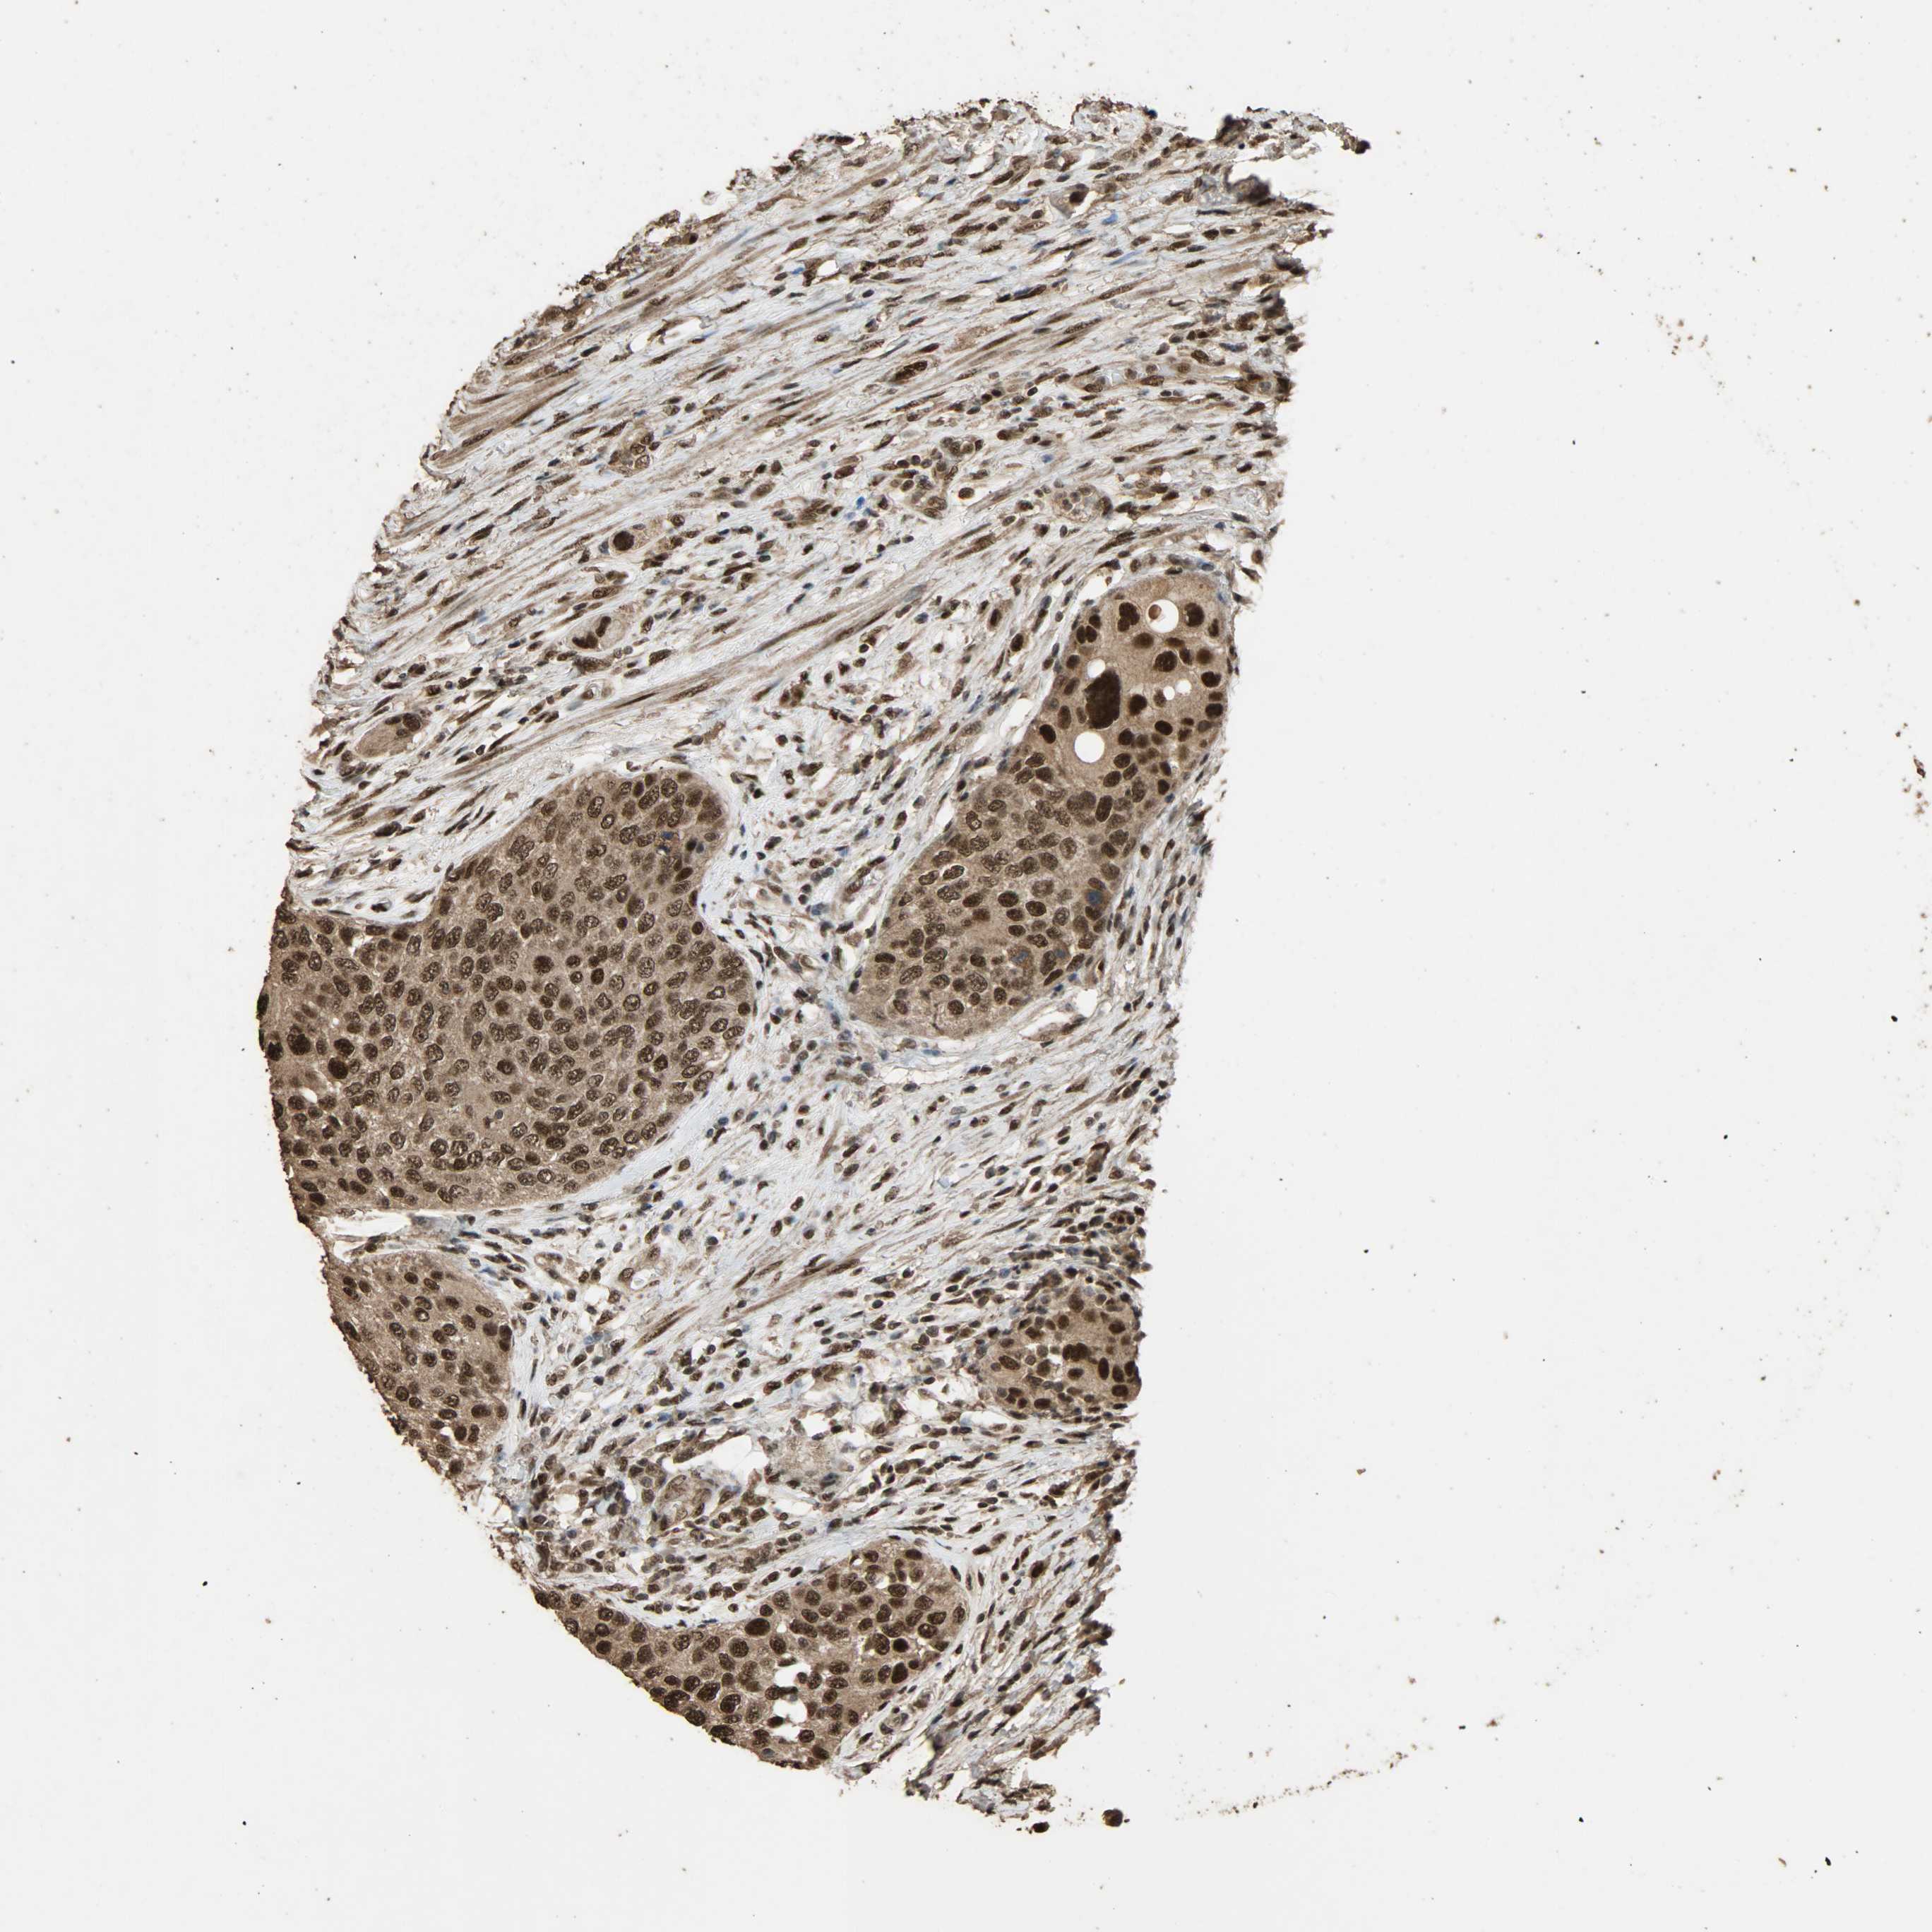

UROTHELIAL CANCER - Protein expressioni

A mouse-over function shows sample information and annotation data. Click on an image to view it in a full screen mode. Samples can be filtered based on level of antibody staining by selecting one or several of the following categories: high, medium, low and not detected. The assay and annotation is described here.

Note that samples used for immunohistochemistry by the Human Protein Atlas do not correspond to samples in the TCGA dataset.

Antibody stainingi

Antibody staining in the annotated cell types in the current human tissue is reported as not detected, low, medium, or high, based on conventional immunohistochemistry profiling in selected tissues. This score is based on the combination of the staining intensity and fraction of stained cells.

Each image is clickable and will lead to virtual microscopy that enables deeper exploration of all samples and also displays staining intensity scores, fraction scores and subcellular localization as well as patient and tissue information for each sample.

Antibody HPA005559

Staining

High

Medium

Low

Not detected

Intensity

Strong

Moderate

Weak

Negative

Quantity

>75%

75%-25%

<25%

None

Location

Nuclear

Cytoplasmic/membranous

Cytoplasmic/membranous,nuclear

Urothelial carcinoma, High grade

Urothelial carcinoma, Low grade